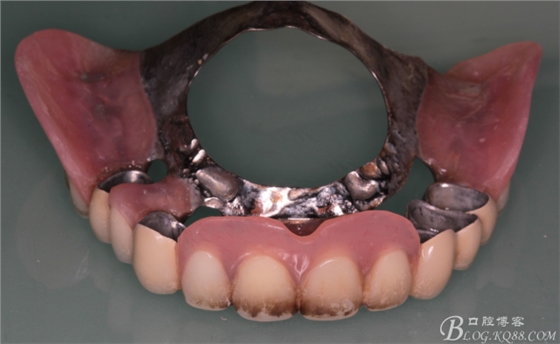

上頜基牙比較分散,選擇 5顆基牙的套筒冠修復(fù),

鈷鉻合金金屬內(nèi)冠

套筒冠外冠

下頜由于44治療之后,松動(dòng)度改善不大,原來(lái)的咬合創(chuàng)傷比較大,不能承擔(dān)較大的(牙合)力,選擇覆蓋義齒,把它磨短平齊牙齦,

其他牙比較集中,選擇雙端球帽式附著體修復(fù)雙端游離缺失

修復(fù)后效果圖,